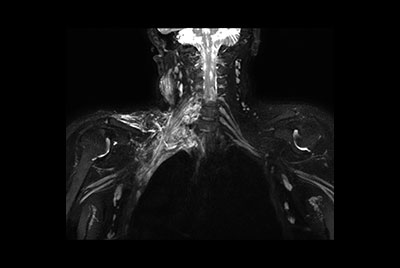

Brachial plexus tumor

Brachial Plexus with a hemangioma

Brachial Plexus lesion